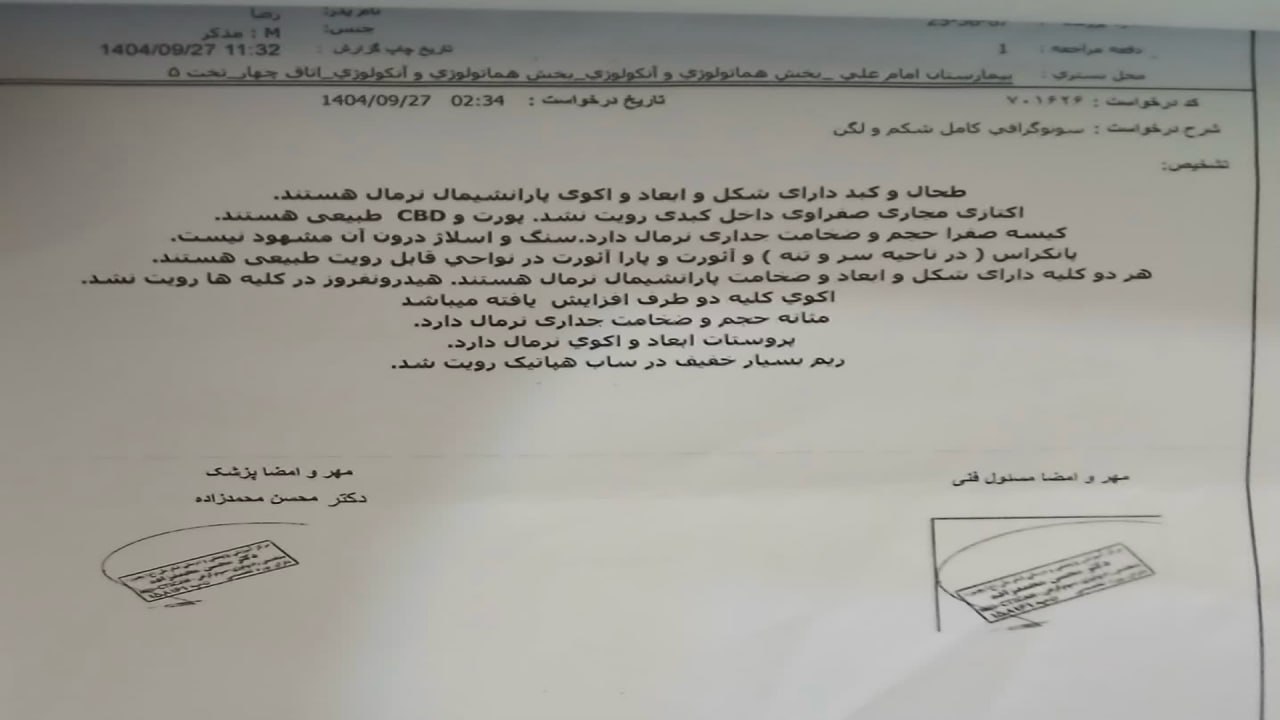

(تصویر مربوط به این مراجعه نیست) Other:

(تصویر مربوط به این مراجعه نیست) Other:

(تصویر مربوط به این مراجعه نیست) Other:

(تصویر مربوط به این مراجعه نیست) Other:

(تصویر مربوط به این مراجعه نیست) Other:

(تصویر مربوط به این مراجعه نیست) Other:

(تصویر مربوط به این مراجعه نیست) Other:

(تصویر مربوط به این مراجعه نیست) Other:

(تصویر مربوط به این مراجعه نیست) Other:

(تصویر مربوط به این مراجعه نیست) Other:

(تصویر مربوط به این مراجعه نیست) Other:

(تصویر مربوط به این مراجعه نیست) Other:

(تصویر مربوط به این مراجعه نیست) Other:

(تصویر مربوط به این مراجعه نیست) Other:

(تصویر مربوط به این مراجعه نیست) Other:

(تصویر مربوط به این مراجعه نیست) Other:

(تصویر مربوط به این مراجعه نیست) Other:

(تصویر مربوط به این مراجعه نیست) Other:

(تصویر مربوط به این مراجعه نیست) Other:

(تصویر مربوط به این مراجعه نیست) Other:

(تصویر مربوط به این مراجعه نیست) Other:

(تصویر مربوط به این مراجعه نیست) Other:

(تصویر مربوط به این مراجعه نیست) Other:

(تصویر مربوط به این مراجعه نیست) Other:

(تصویر مربوط به این مراجعه نیست) Other:

(تصویر مربوط به این مراجعه نیست) Other:

(تصویر مربوط به این مراجعه نیست) Other:

(تصویر مربوط به این مراجعه نیست) Other:

(تصویر مربوط به این مراجعه نیست) Other:

(تصویر مربوط به این مراجعه نیست) Other:

(تصویر مربوط به این مراجعه نیست) Other:

(تصویر مربوط به این مراجعه نیست) Other:

(تصویر مربوط به این مراجعه نیست) Other:

(تصویر مربوط به این مراجعه نیست) Other:

(تصویر مربوط به این مراجعه نیست) Other:

(تصویر مربوط به این مراجعه نیست) Other:

(تصویر مربوط به این مراجعه نیست) Other:

(تصویر مربوط به این مراجعه نیست) Other:

(تصویر مربوط به این مراجعه نیست) Other:

(تصویر مربوط به این مراجعه نیست) Other:

(تصویر مربوط به این مراجعه نیست) Other:

(تصویر مربوط به این مراجعه نیست) Other:

(تصویر مربوط به این مراجعه نیست) Other:

(تصویر مربوط به این مراجعه نیست) Other:

(تصویر مربوط به این مراجعه نیست) Other:

(تصویر مربوط به این مراجعه نیست) Other:

(تصویر مربوط به این مراجعه نیست) Other: